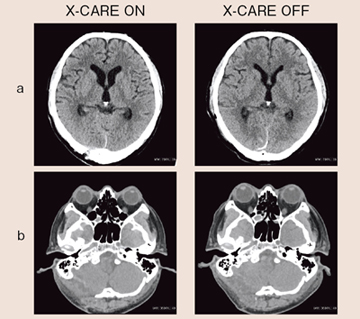

●頭部単純CTの症例提示

図8aは脳実質レベルの画像,図8bは水晶体レベルの画像である。どちらも目立ったアーチファクトはなく,診断に問題のない画像だった。

図8 頭部単純CT(56歳,男性)